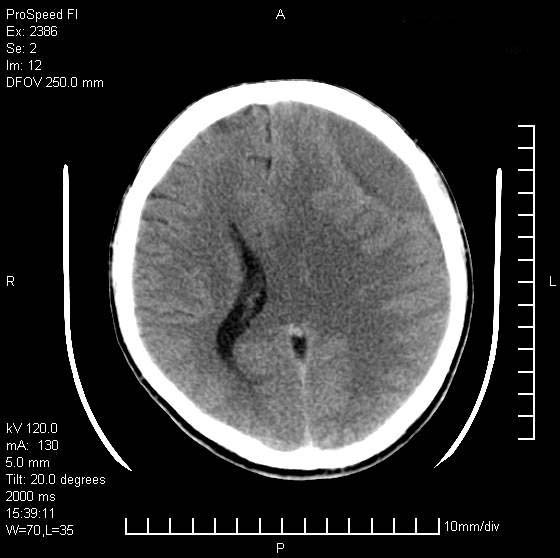

以下是引用天南地北在2007-9-19 18:43:00的发言:[br]典型慢性硬膜外血肿[br][br][本贴已被 天南地北 于 2007-9-19 18:44:11 修改过]

以下是引用曼一拍在2007-9-20 11:06:00的发言:[br]支持慢性硬膜下血肿.[br]慢性硬膜下积液:血肿有包膜,ct值稍高于脑脊液,增强可有染色。不典型者血肿可多呈梭形.是硬脑膜与蛛网膜之间的潜在腔隙内的血肿。[br]鉴别:[br]1\\硬膜外血肿:是颅脑外伤后脑膜或板障内血管破裂,血液在颅骨与硬膜之间积聚所致.通常是脑膜动脉破裂,也可因静脉窦破裂或颅骨的板障静脉出血,发生于外伤的着力部,常与颅骨骨折并存。脑膜动脉出血则急,若是板障静脉出血在则可有慢性。[br]2\\硬膜下积液:(硬膜下水瘤)[br]是由于蛛网膜破裂,脑脊液经蛛网膜破口进入硬膜下腔不能回流。或水肿阻塞而形成。[br]ct表现:颅骨内板下方新月形低密度区近似脑脊液密度;占位效应清,周围无脑水肿。[br]